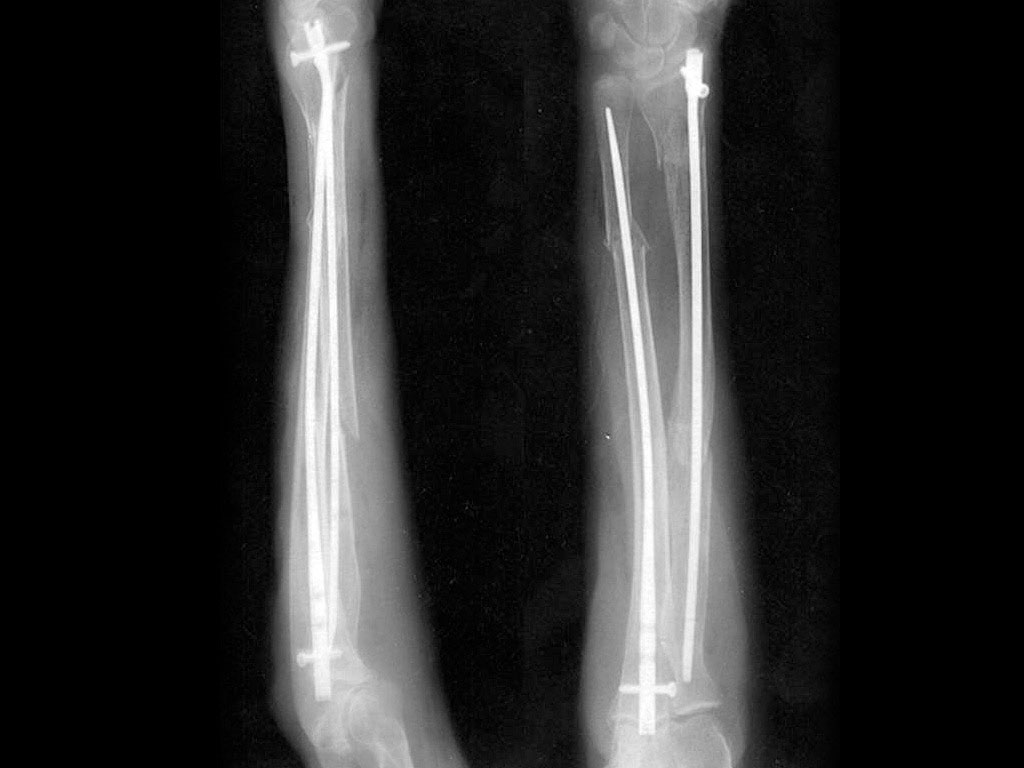

The Acumed Forearm Rod System offers surgeons an alternative option for the treatment of fractures and osteotomies of the radius and ulna over traditional plating. Each fluted rod is designed to be inserted through a small incision with minimal canal reaming. A targeted interlocking screw, combined with a paddle blade tip design, locks and rotationally secures the bone segments to assist in fracture union.

The rod’s paddle-blade tip and interlocking screws are designed to lock and rotationally secure bone segments to assist in fracture union.

Rods are precontoured to match the ulnar and radial canal’s geometry.

X-Ray